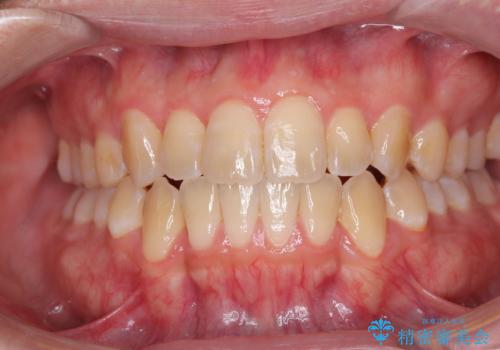

治療を長期化させたくないとのご要望があったので、左下の90度捻転した歯は、捻転した状態のゴールとしました。

反対咬合を改善したことで、歯ぎしりしたときの引っかかる感じがなくなり、奥歯への負担を大きく軽減することができました。